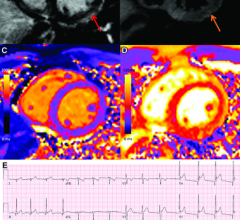

A 26-year-old man with history of diabetes and hypertension presented with 7 days of fever, chills, nausea, intractable ...

February 15, 2022 — Vaccine-associated myocarditis shows a similar injury pattern on cardiac MRI compared to other ...

February 17, 2022 — While cardiac imaging shows that COVID-19 vaccine–associated myocarditis has a similar pattern as ...